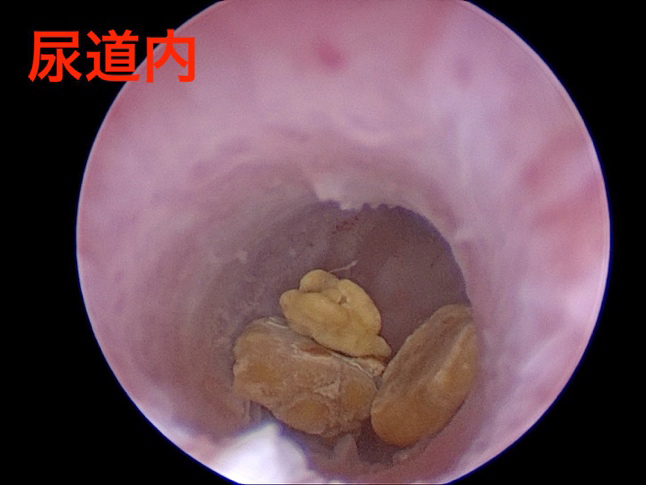

尿道内の石を確認しカテーテルで膀胱内に押し戻した様子